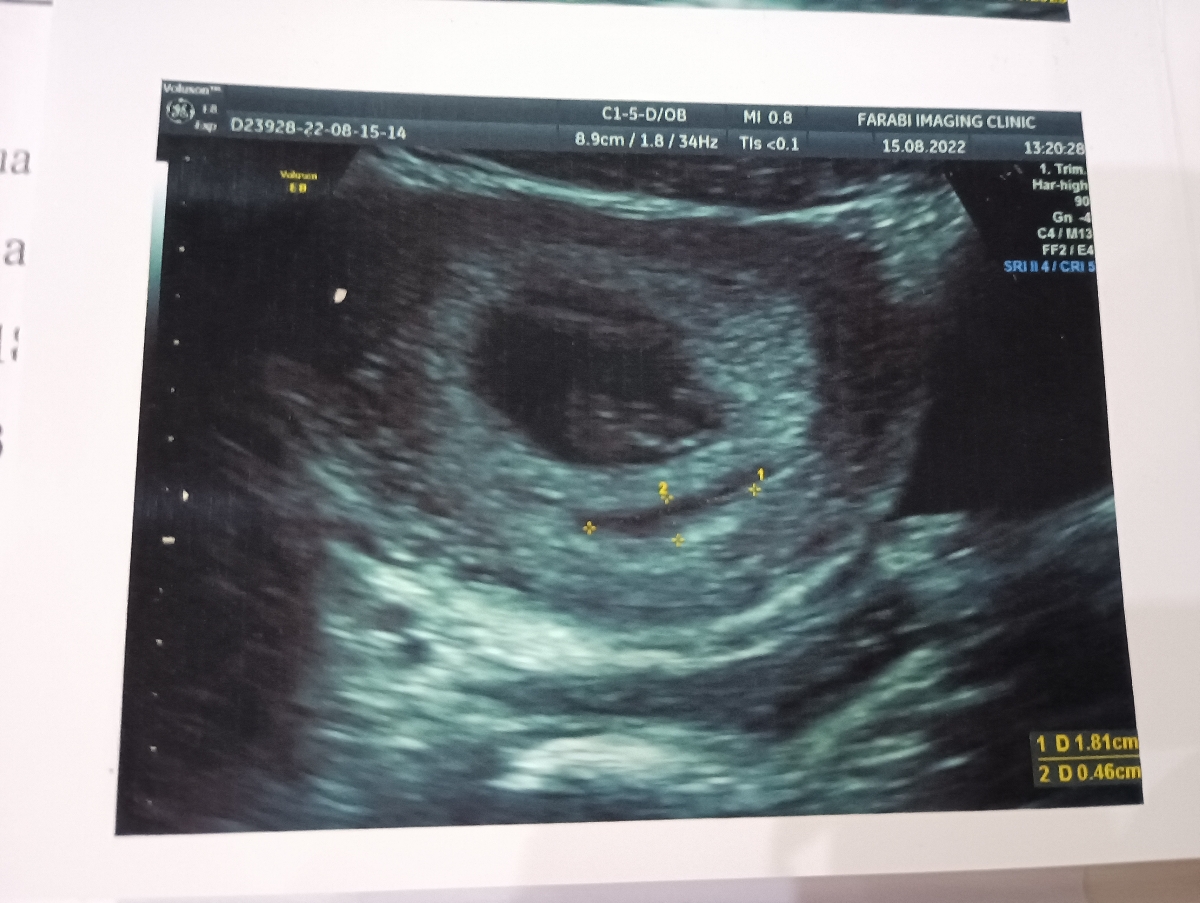

سلام وقتتون بخیر من امروز سونو قلب دادم خدا رو شکر گفتن نرماله فقط گفتن هماتوم دارم به اندازه ذکر شده .

جواب سونو قلب هفته ۸ . داشتن هماتوم

باتوجه به هماتوم و طول سرویکس ( در سونوگرافی شکمی آن هم در هفته 12 طول سرویکس دقیق نیست ولی در هر حال با توجه به عدد گزارش شده باید در مورد شما دقت و نظارت بیشتری داشت)، حتماً استراحت بسیار زیاد داشته باشید، از پله تا حد امکان بالا پایین نروید، با رعایت سبک زندگی صحيح مانع بروز یبوست شده و از سرویس بهداشتی فرنگی استفاده نمایید ،سفر و پیاده روی طولانی برای شما ممنوع است و به علاوه نزدیکی و دخول و همچنین به ارگاسم رسیدن و تحریک سینه ها نیز برای شما ممنوع هستند تا زمانی که بتوان با تکرار سونوگرافی در هفته های بالاتر اطلاعات دقیق تری نسبت به طول سرویکس و شرایط شما به دست آورد. آزمایشات ابتدایی بارداری انجام شده؟